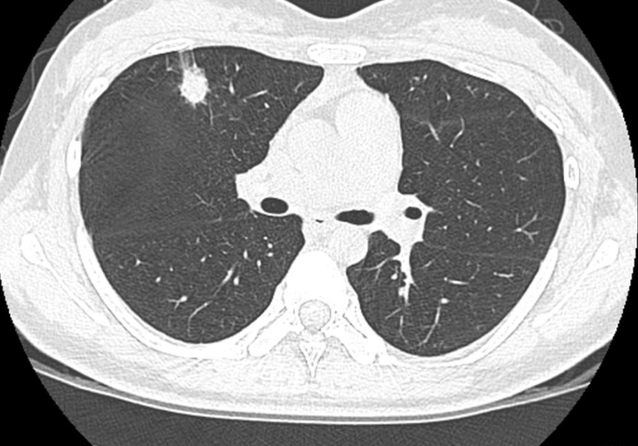

检测的结果让李大叔大吃一惊,原来自己的肺部竟然出现了小的病灶面积,大约在1.26×0.83左右。

经过综合的分析和诊断,医生断定为是肺结节,建议李大叔选择保守治疗的方式,可以给他省不少的钱,如果后期病灶发展再进行手术治疗。